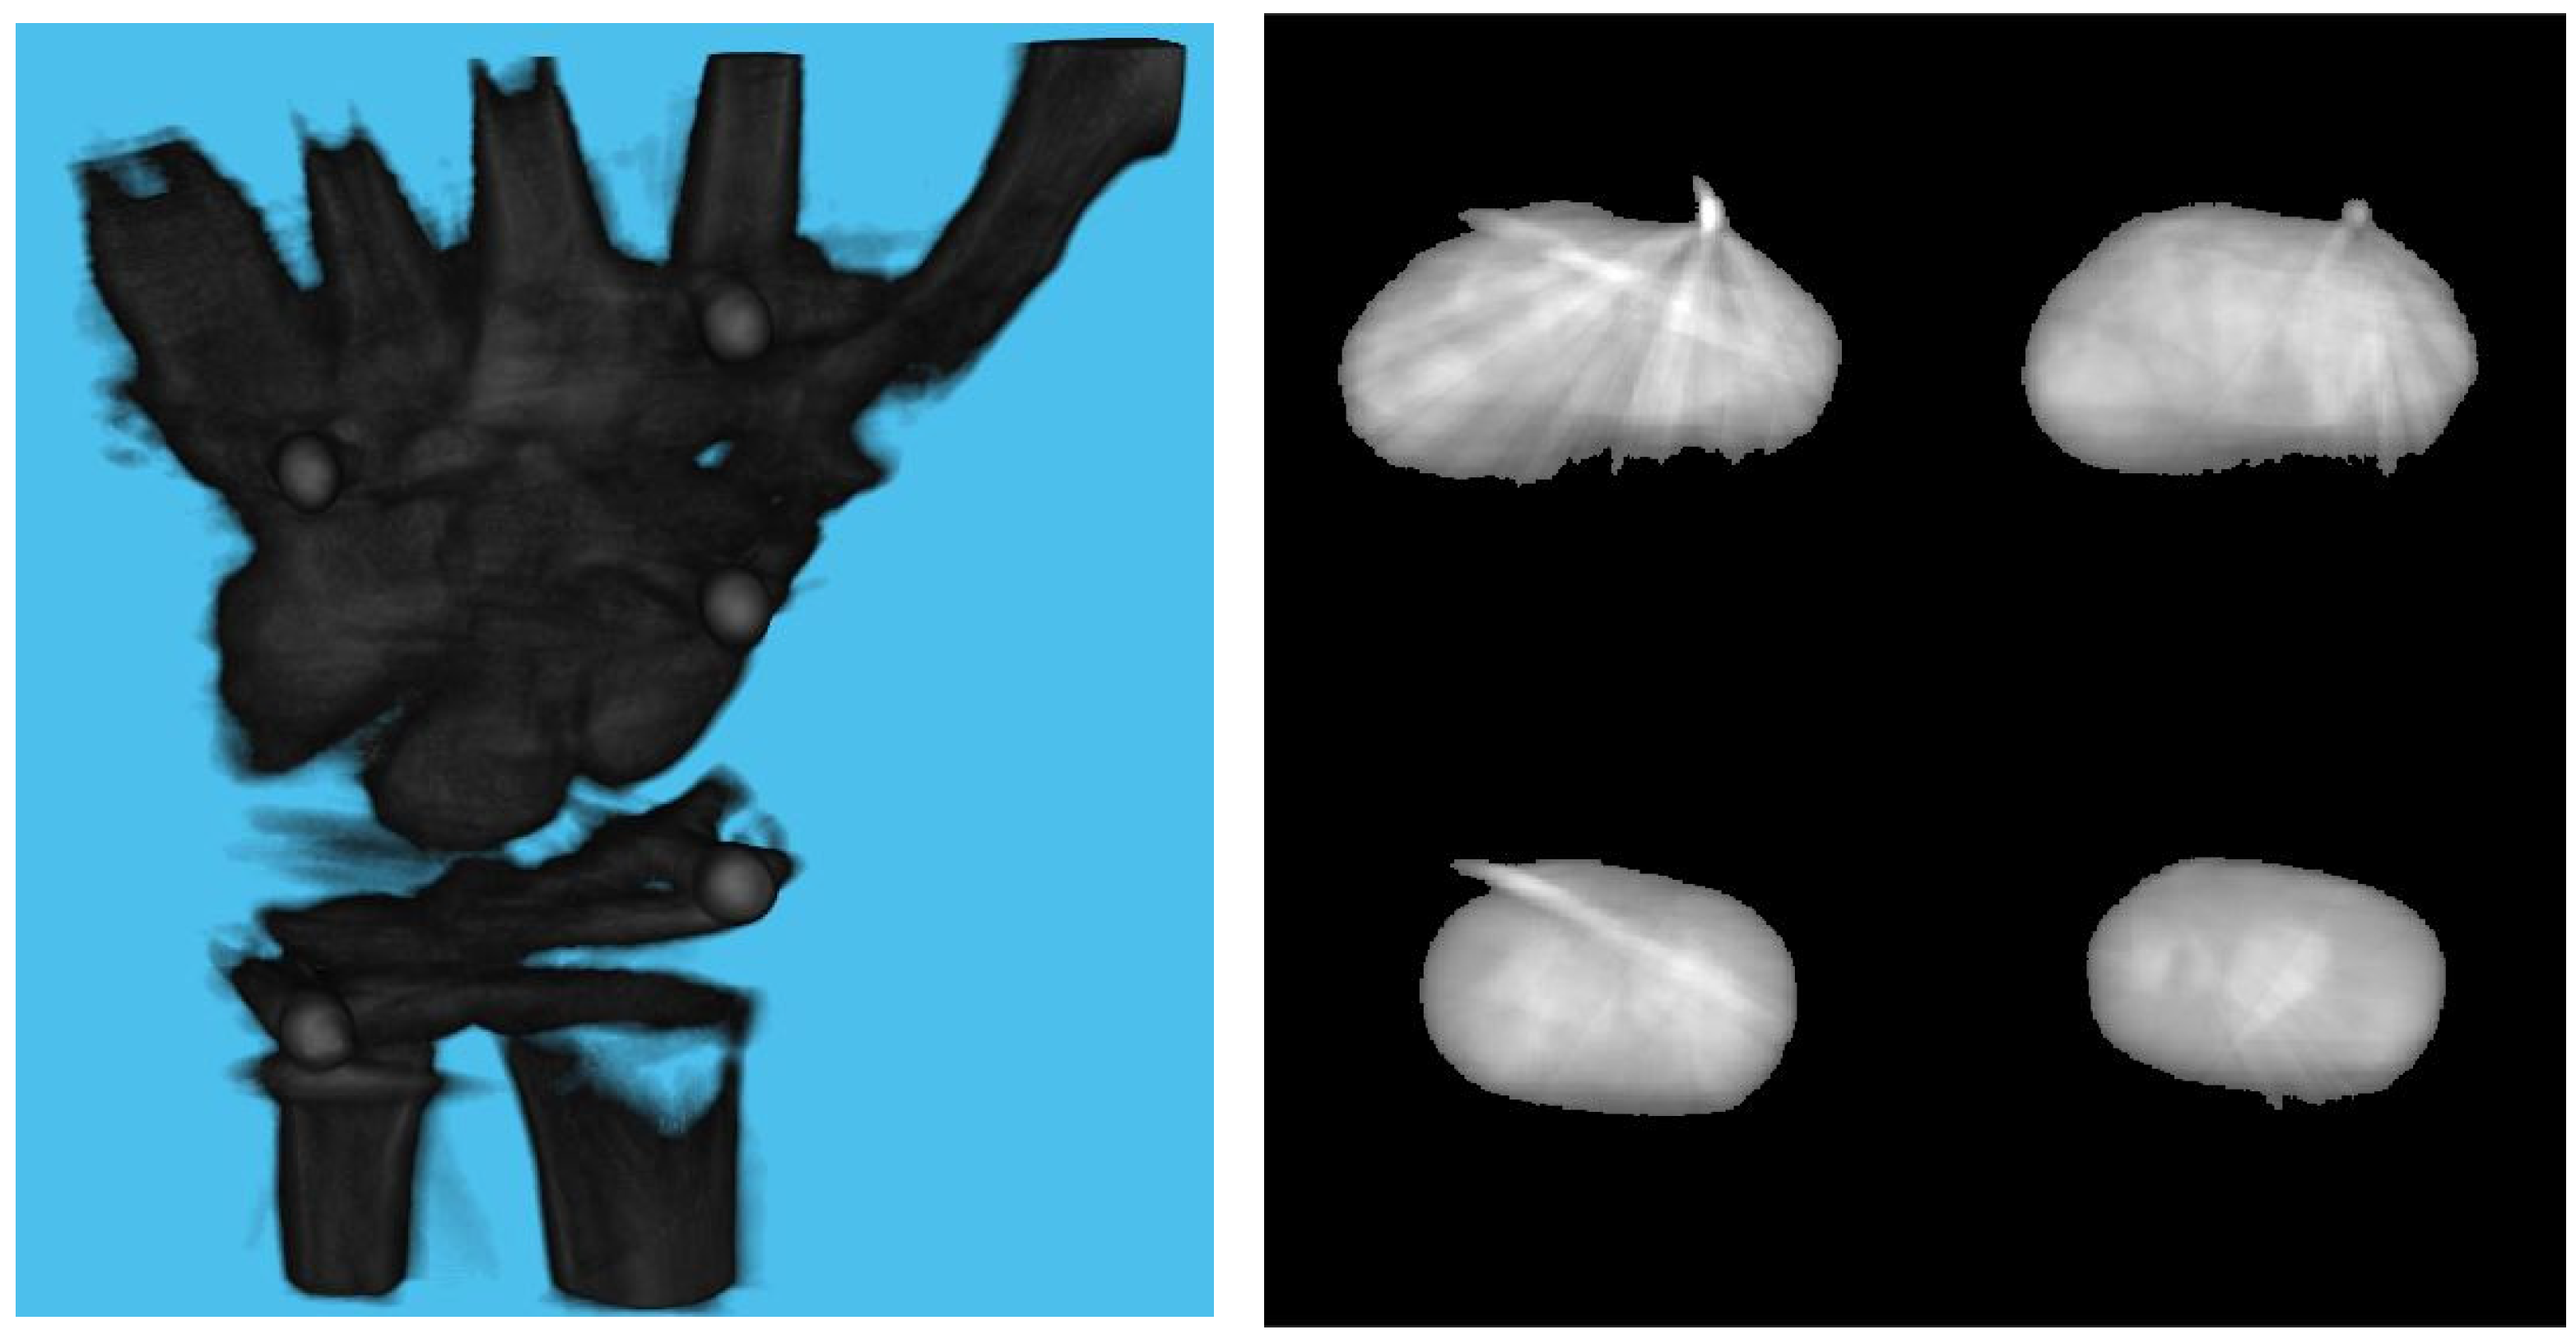

3.1. Simulation Setup

3.2. Effect of Board Thicknesses and Marker Sizes on Reconstructed Image Quality